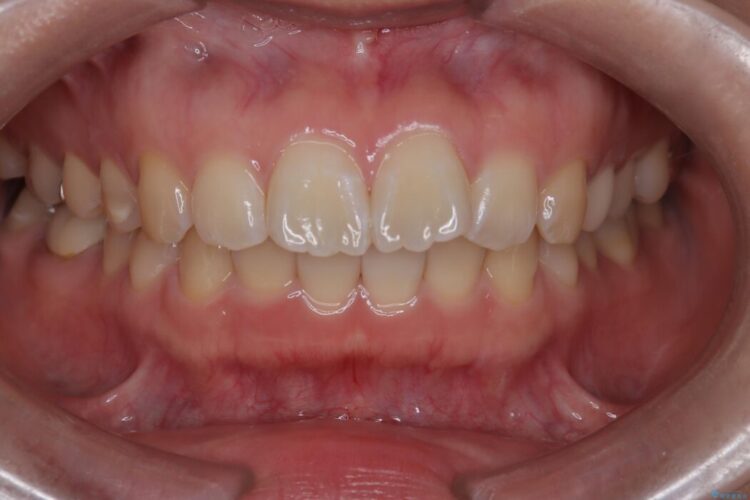

治療後について

今回の矯正治療では、前歯を大きく後退させるスペースを確保するため、計画通り上下左右の第一小臼歯を抜歯しました。

装置には、上顎には目立たない裏側矯正(舌側矯正)を、下顎には透明な審美ブラケットを使用するハーフリンガル矯正を採用しました。抜歯によってできたスペースを最大限に活用し、前歯を効率よく後方へ移動。治療の結果、口元の突出感が大幅に解消され、Eライン(横顔の美しさの基準)も改善しました。人目を気にすることなく治療を完遂し、自信の持てる美しい横顔を獲得していただけました。